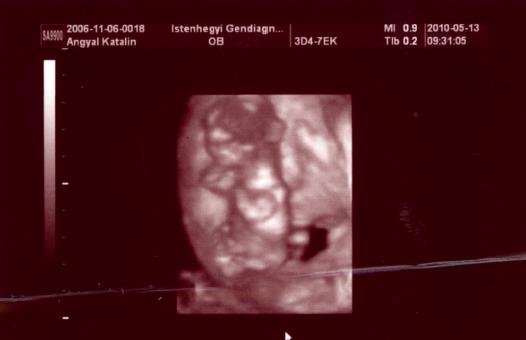

Angie, nagyon örülök, hogy mindenk okés volt tegnap HK-nál! most már fellélegezhetsz, szerencsére minden okés a kisbabáddal!